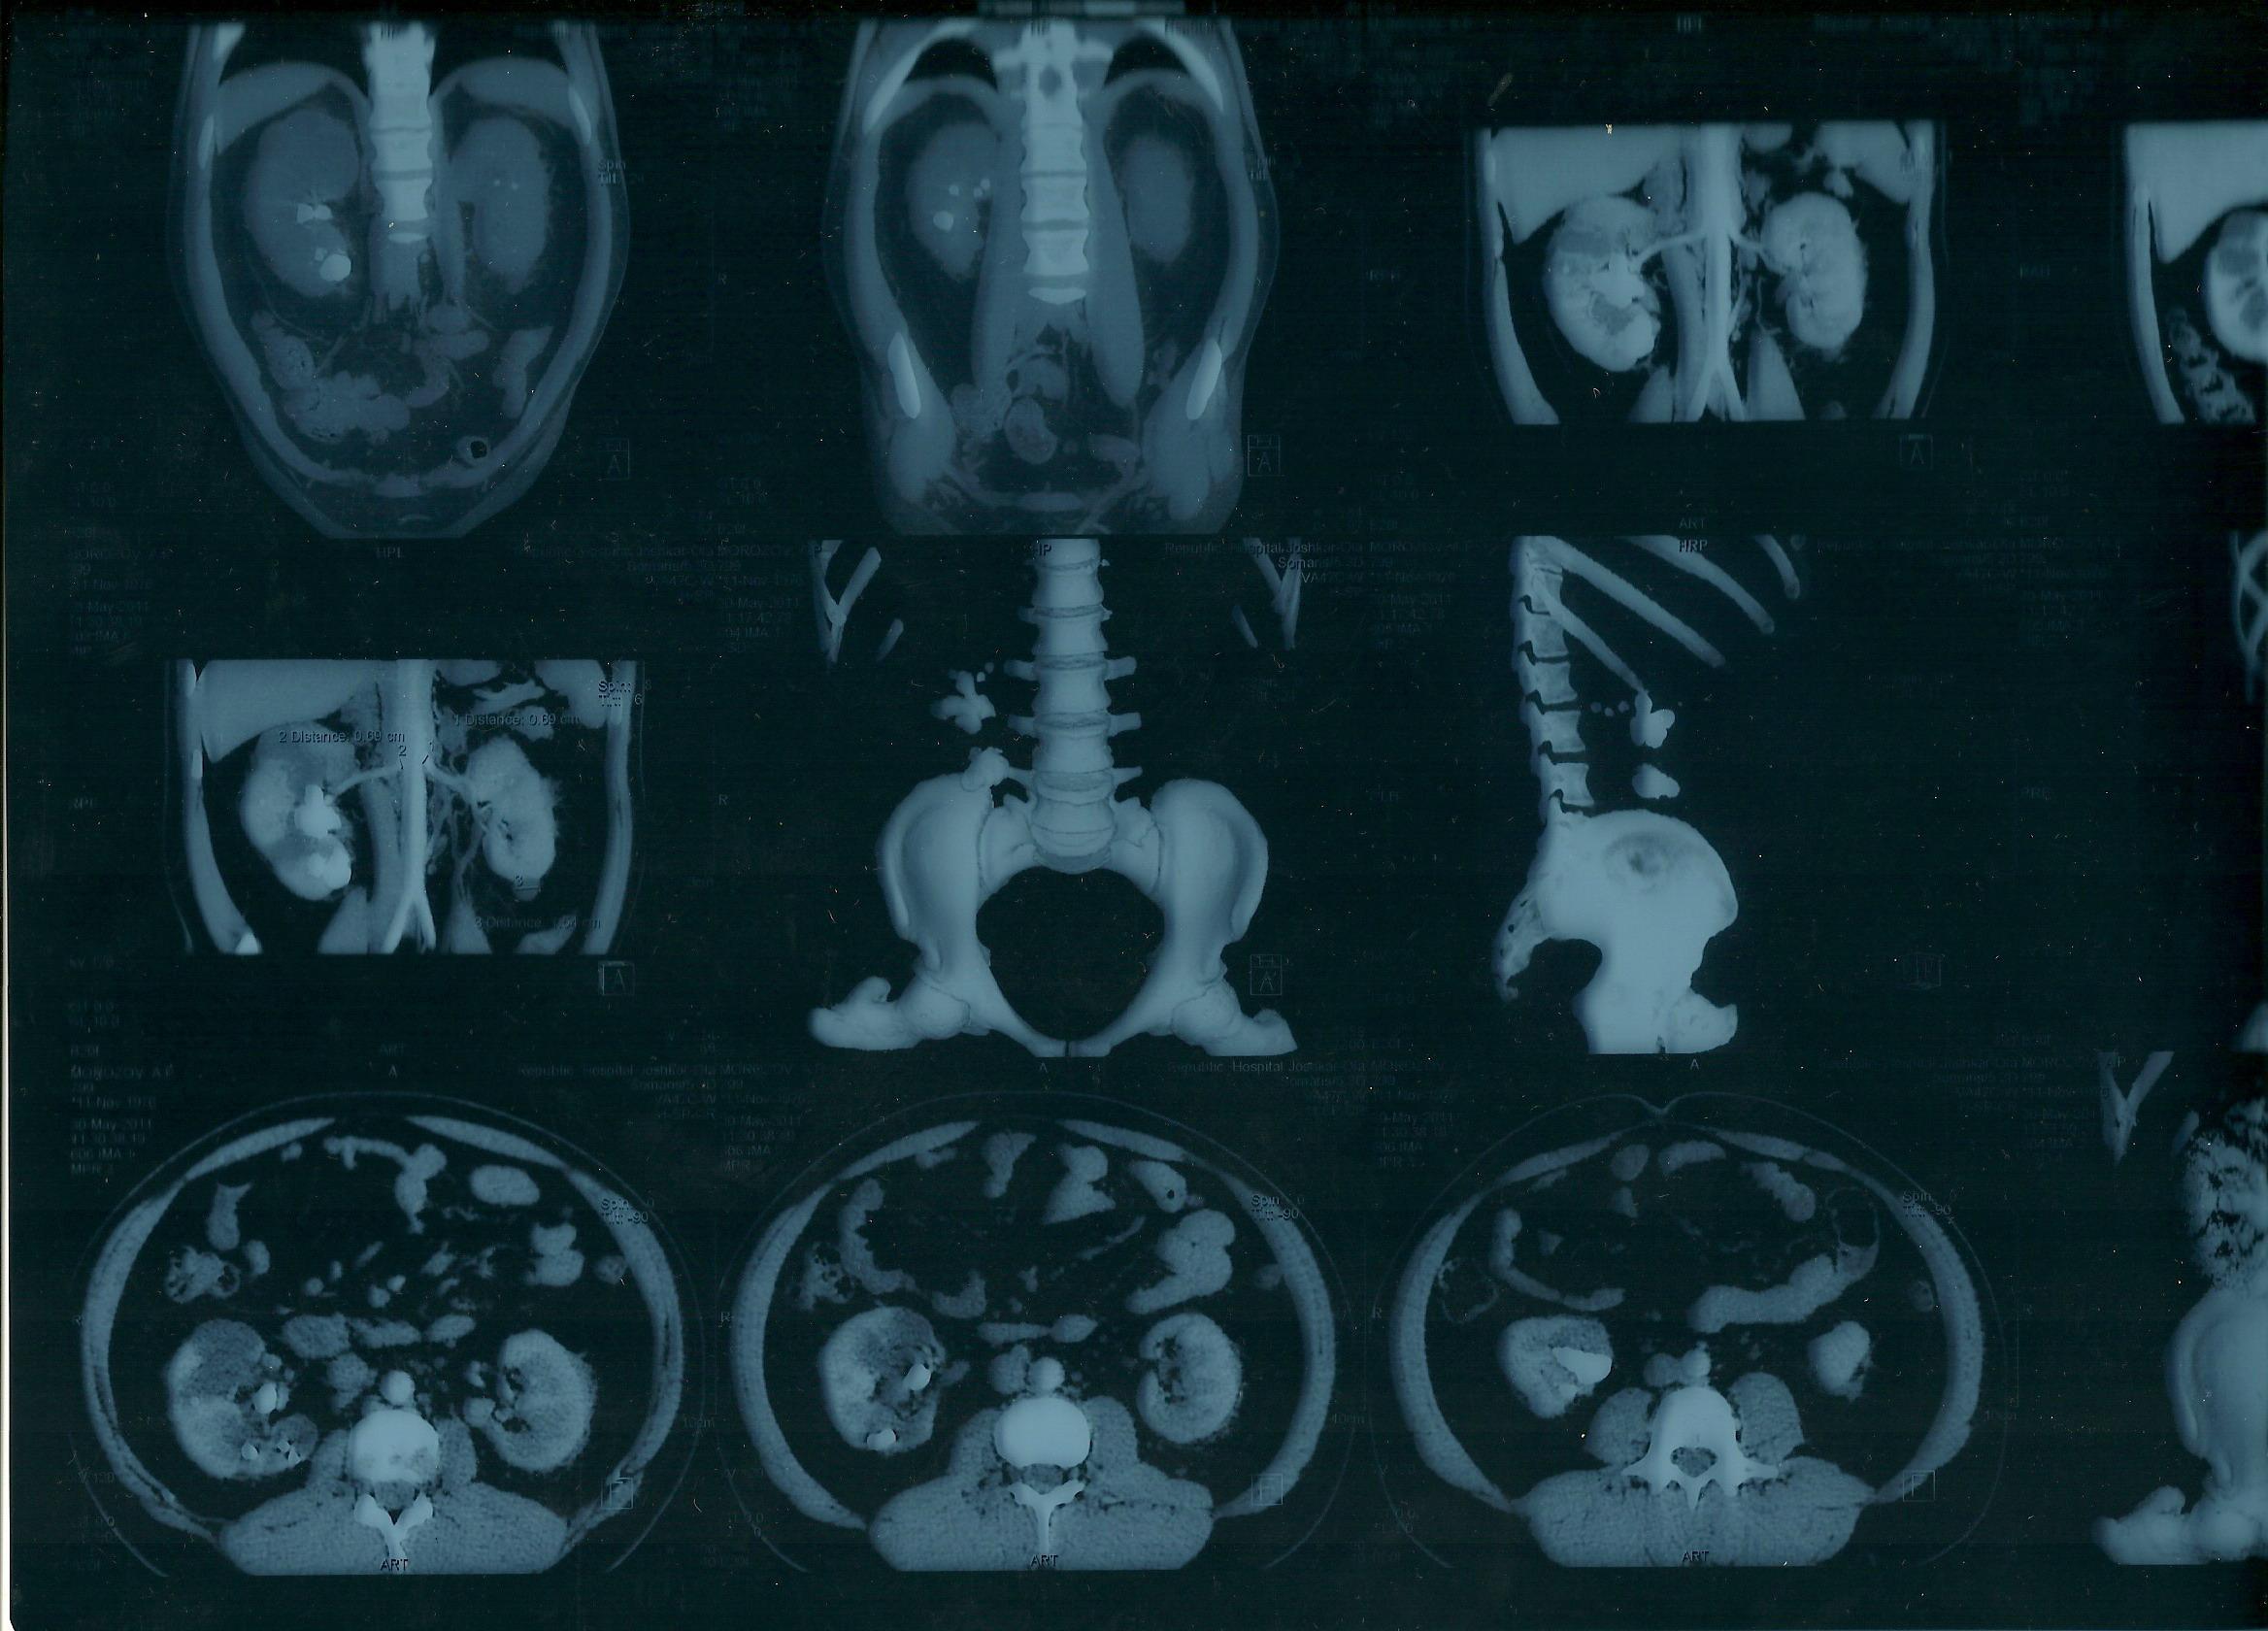

Морозов Алексей. Здравствуйте,находился

на лечении в урологическом отделении

г.Йошкар-Ола по поводу МКБ, В правой почке

обнаружен коралловидный камень,врач

рекомендовал ЧПНЛ в Нижнем Новгороде,но

дело в том что у меня гемофилия,возможно

ли провести данную операцию?